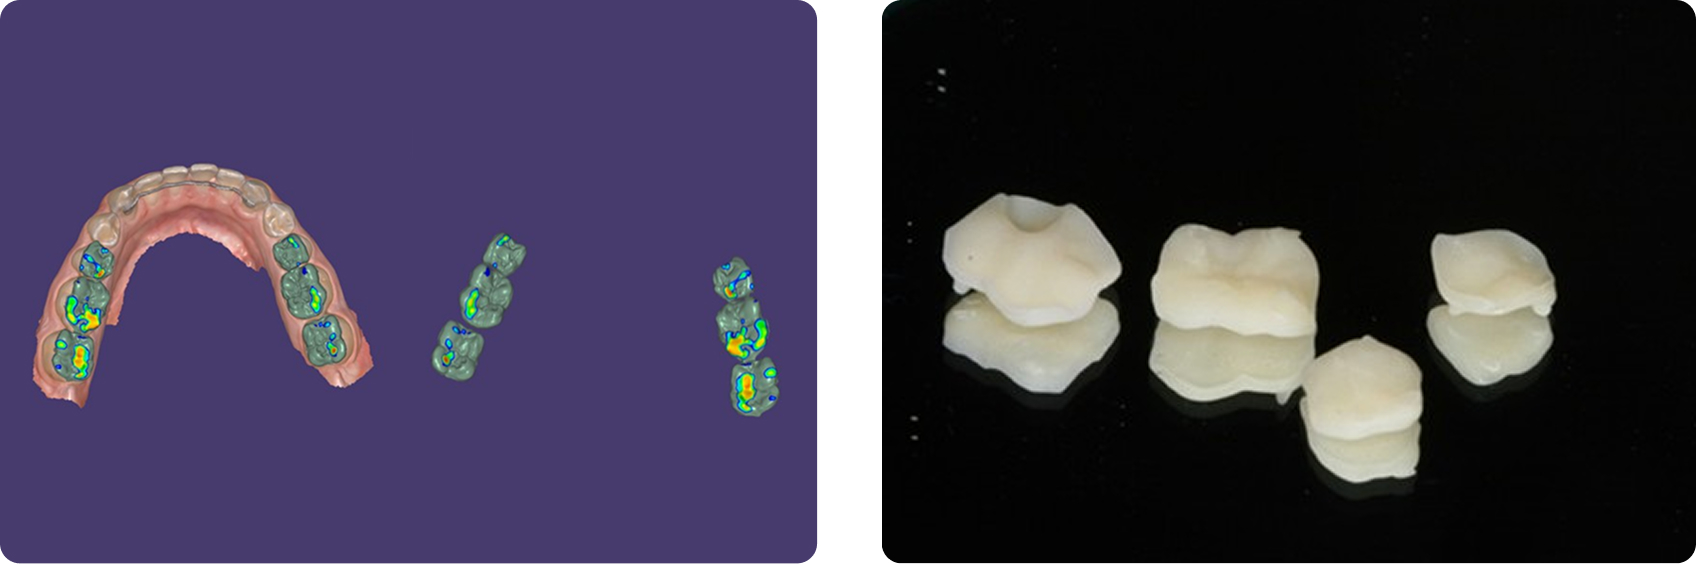

Digital scans were used to create a diagnostic wax-up and design posterior resin onlays (Fig. 9). Teeth were air-abraded to enhance adhesion, and onlays were bonded without tooth preparation.

Occlusion was equilibrated, followed by direct composite restoration of the anterior teeth, with emphasis on lingual contours to support the increased VDO (Fig. 10).